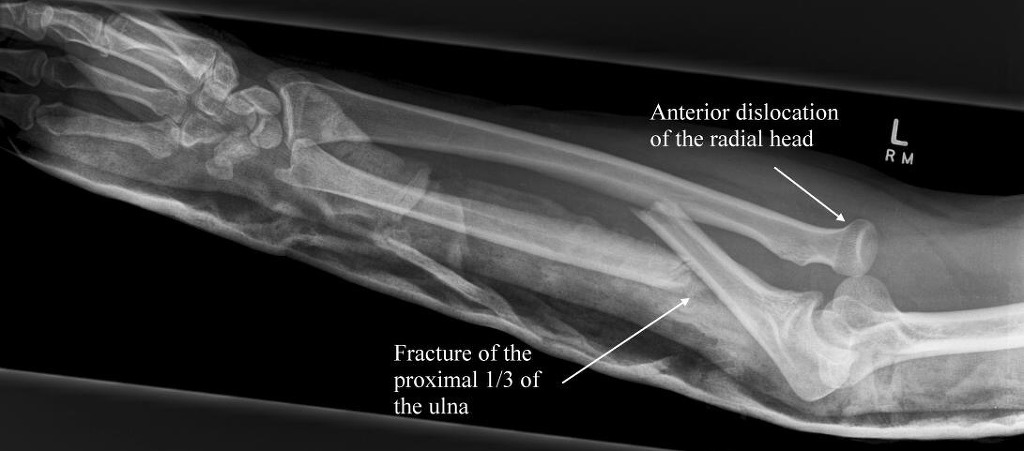

12. 몬테기아 골절(Monteggia fracture)과 연관된 현상에 대해 기술하라.

몬테기아 골절(Monteggia fracture)은 요골두의 아탈구 또는 탈구를 동반한 근위 척골의 골절을 말한다. 이 골절과 탈구는 원래 1814년 몬테기아에 의해 처음으로 기술되었다. 근위 척골의 골절을 볼 때, 동반된 요골두의 탈구 또는 아탈구를 보는 것을 기억하는 것이 중요하다. 왜냐하면 요골두의 괴사가 초래될 수 있다는 사실을 놓칠 수 있기 때문이다.

몬테기아 골절 (이미지 출처 : http://cdn.lifeinthefastlane.com)